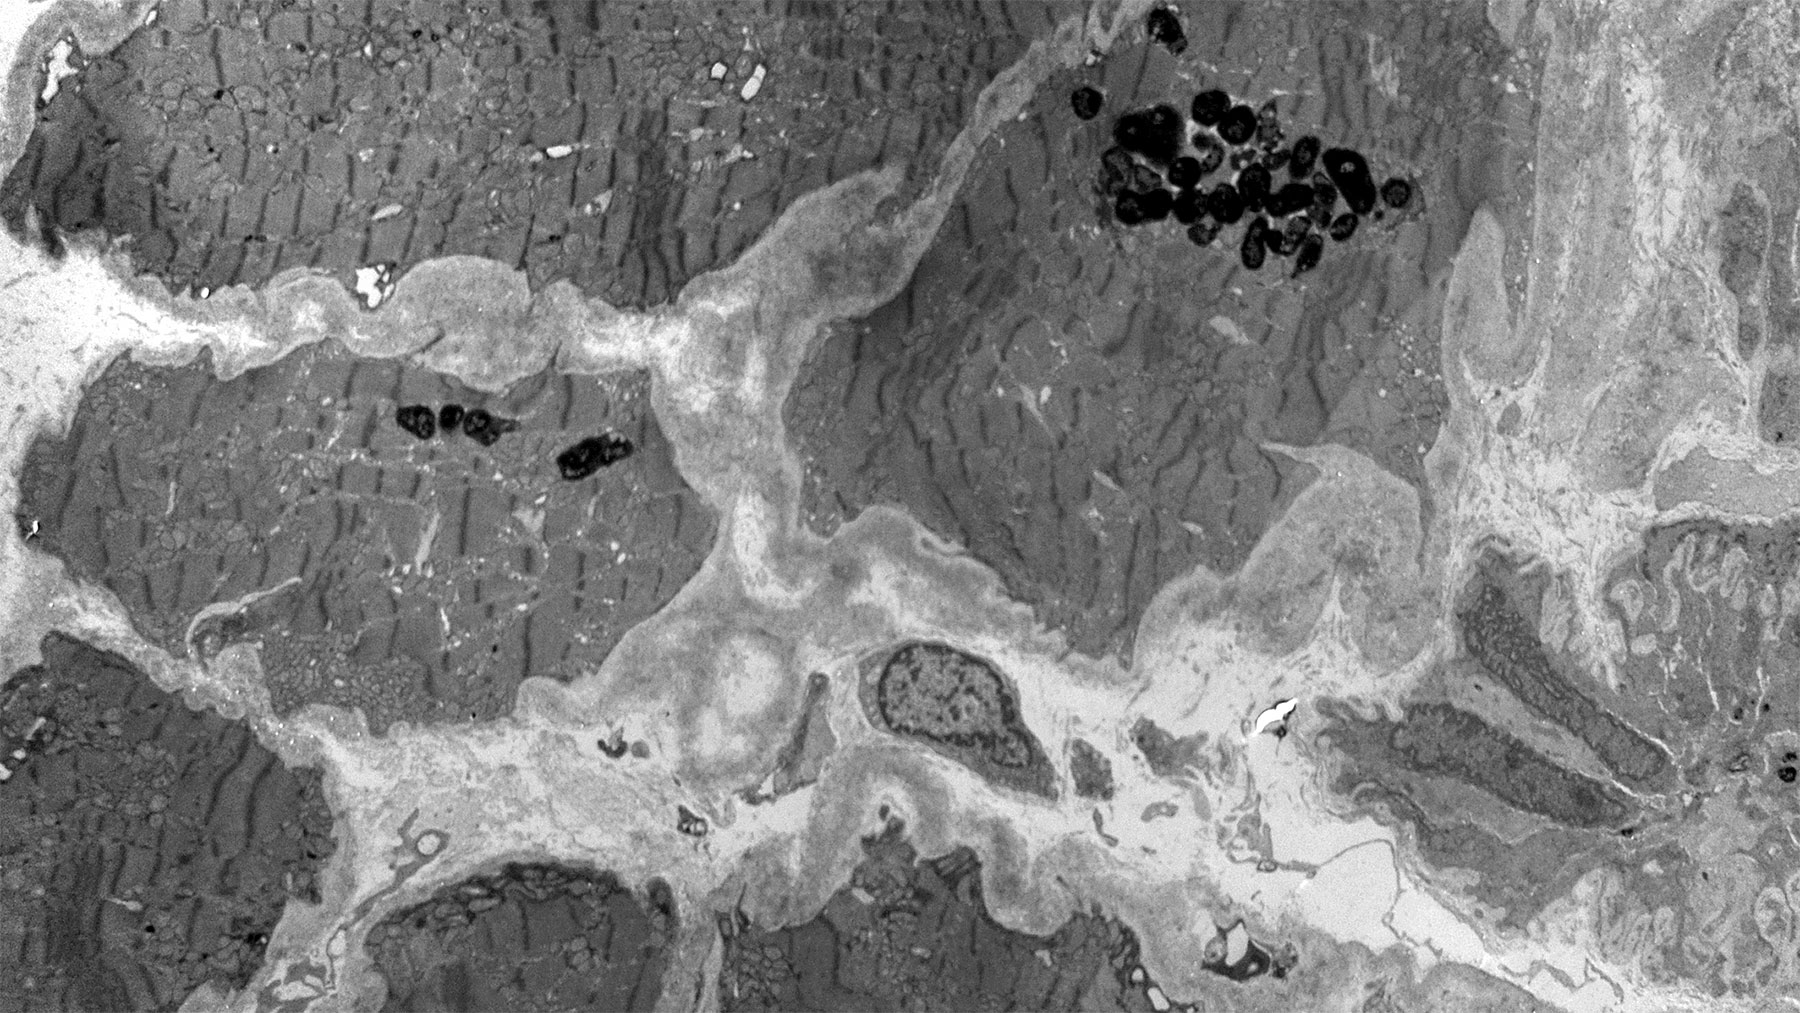

Figure G. Electron Microscopy

Histology: A heart biopsy was performed and H&E sections (Figures A & B) show myocardial tissue with unremarkable cardiomyocytes and mild to moderate interstitial fibrosis, confirmed by trichrome staining (Figures C and D). The small vessels show moderate wall thickening with accumulation of smudgy, light eosinophilic material with cracking appearance, which stains light purple with the trichrome staining. Congo red staining (Figure E) viewed under polarized light shows apple-green birefringence consistent with amyloid deposits. Electron microscopic examination (Figures F and G) reveal cardiomyocytes and vascular structures surrounded by a fibrillary material (Figure G) consistent in size and appearance with amyloid (n 5-15 nanometer).